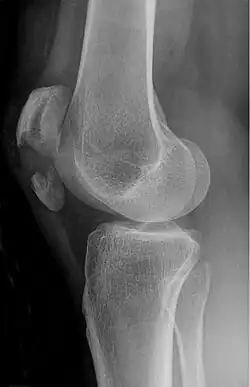

Comminuted fracture of patella -